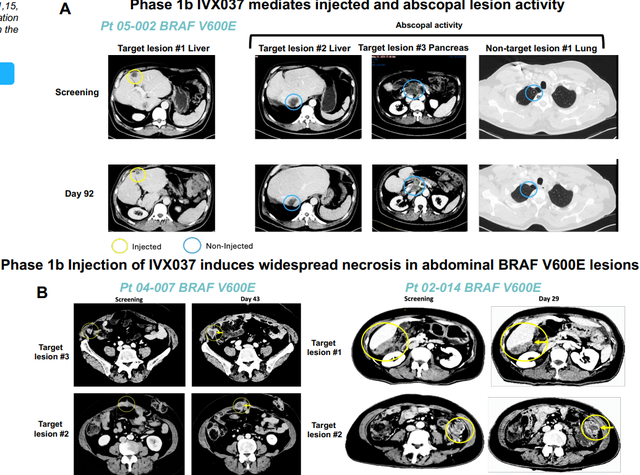

IVX037是一种非基因改造的溶瘤小RNA病毒,此次会议上公布了IVX037在晚期微卫星稳定型(MSS)结直肠癌(CRC)的I期研究结果。结果显示:在首批9名携带KRAS或BRAF突变的患者中,有6名实现了疾病控制,在携带KRAS或BRAF突变的患者中,33个目标病灶中有21个(64%)实现了疾病控制;而在野生型患者中,10个目标病灶中仅有1个(10%)实现疾病控制。

在Ib期联合研究的第二名卵巢癌患者中也观察到了早期临床活性。该例BRCA2突变患者实现了持久的、持续的部分缓解(PR),并伴随血清CA-125水平的显著下降。

IVX037治疗在一些结直肠癌患者中显示出对肝脏、胰腺和肺部转移灶的显著控制效果,在BRAF V600E患者的腹部病变中诱导了快速且广泛的细胞坏死。